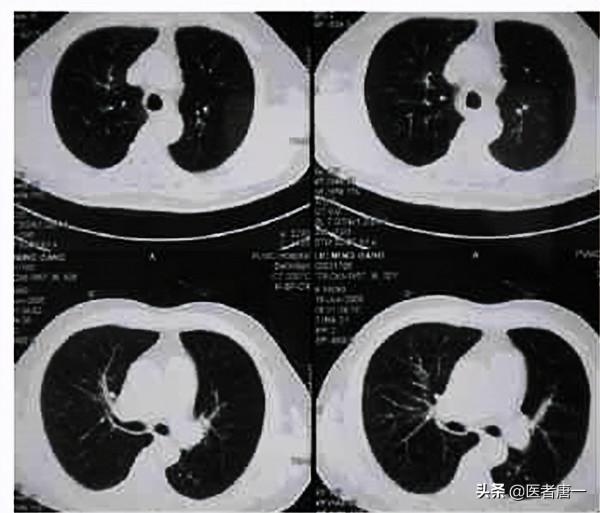

透過李叔叔的描述以及CT和肺功能的結果,醫生最終給李叔叔診斷為“慢性阻塞性肺疾病”,也就是平時老百姓常說的“老慢支”。由於李叔叔正處於急性炎症期,醫生便建議李叔叔住院治療幾天。在住院的這幾天,李叔叔除了接收消炎治療外,每天都會有護士長親自帶著他們慢阻肺的病人們一起做呼吸鍛鍊,從吹氣球,到呼吸操,再到唱歌。